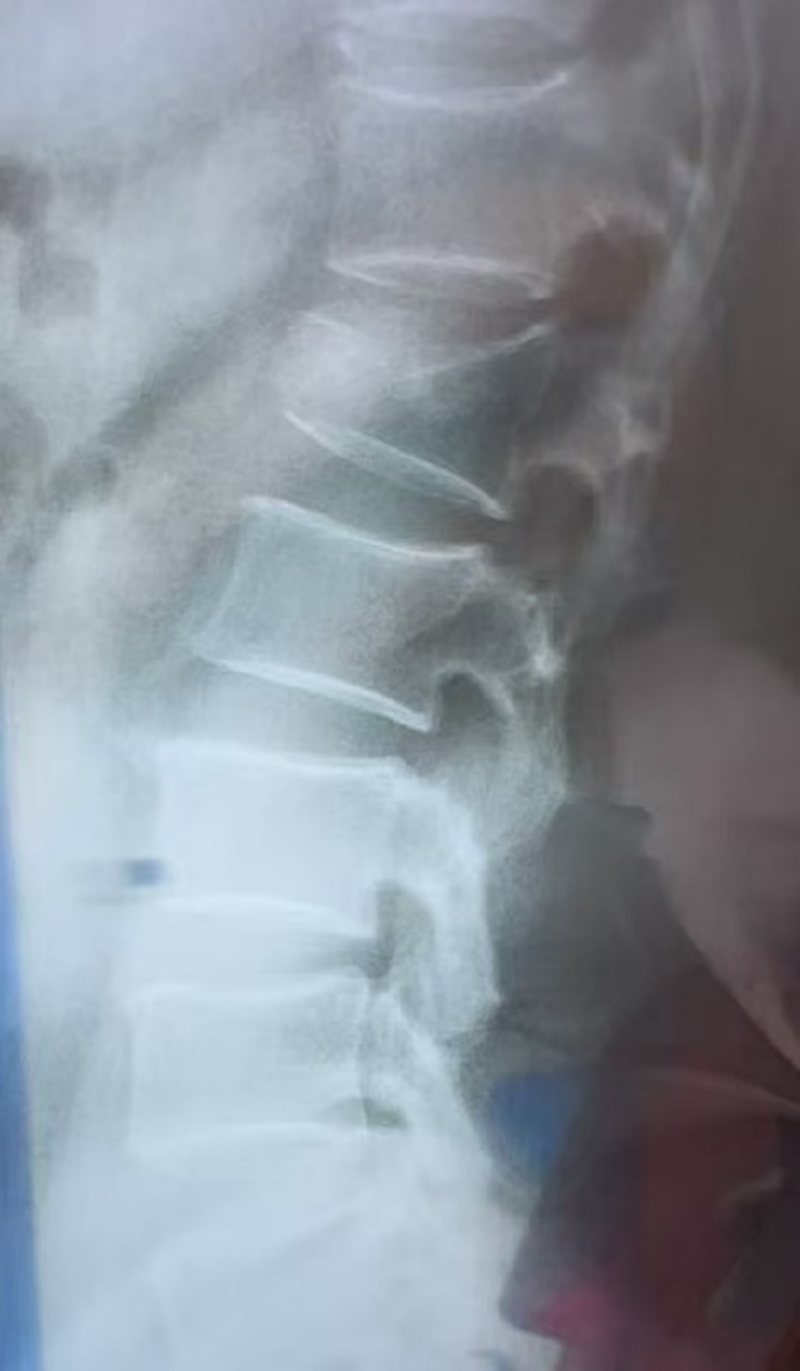

患者于9月10日因“外伤致腰部活动受限数小时”入院。据了解,患者不慎摔伤后腰部剧痛、活动障碍,经腰椎影像学检查,提示“椎体爆裂性骨折”。患者随即到同济军山运动医学中心寻求专业救治。中心门诊迅速明确诊断为“腰椎爆裂性骨折 (Lumbar Burst Fracture)”,并立即安排其住院。